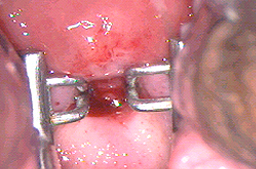

Cuando se utiliza en vagina, vulva y pene puede dar una profundidad mayor de la deseada y ocasionar problemas de cicatrización como se observa en las imágenes, o perforaciones del tejido hacia vejiga y/o recto.